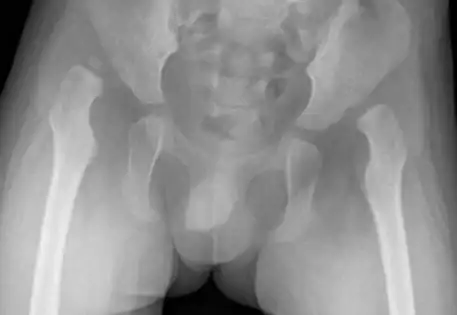

What is the outcome following single-stage hip reconstruction?

Surgical outcomes for late-presenting hip dislocations are typically associated with the age of diagnosis, with less favorable results reported for older children in the literature. Dr. Qureshi employs a single-stage hip reconstruction technique, addressing all deformity elements comprehensively rather than solely focusing on hip relocation. Dr. Qureshi is pleased to showcase successful cases treated with this advanced approach.